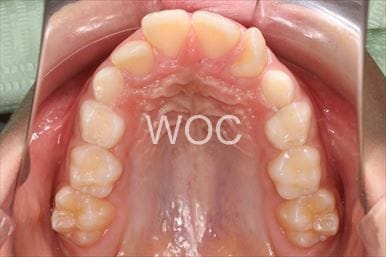

治療前1

治療後1